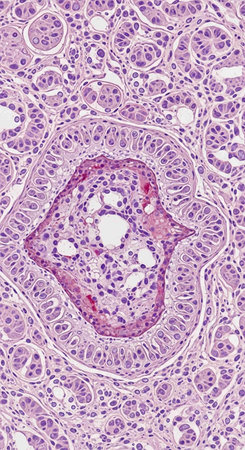

Photomicrograph showing histological features of benign prostatic hyperplasia. Enlarged prostate gland with nodular proliferation of glandular and stromal components.

Photomicrograph showing histological features of benign prostatic hyperplasia. Enlarged prostate gland with nodular proliferation of glandular and stromal components.